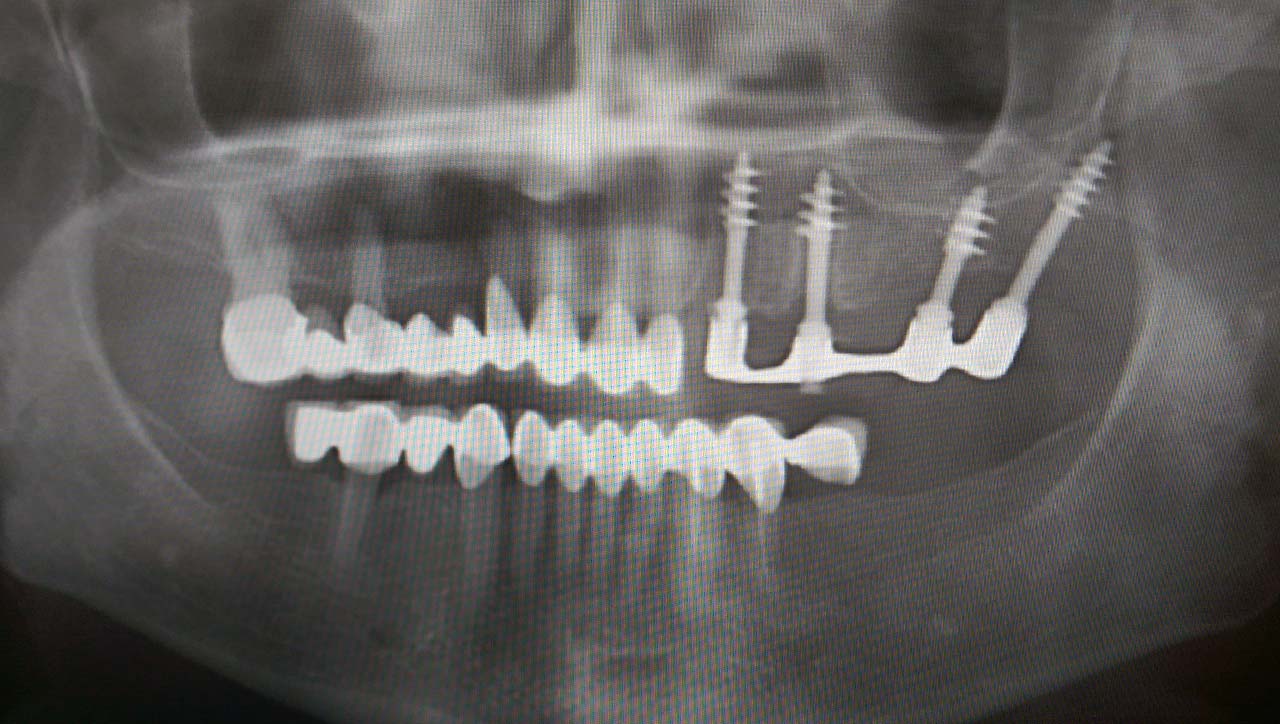

Teljes szájüregi rehabilitáció két lépésben

Ismét egy teljes szájüregi rehabilitáció két lépésben. Először az alsó fogak lettek kihúzva és azonnal implantálva, híddal ellátva, majd később a felső. IHDE svájci azonnal terhelhető implantátumok és cirkónium hidak. Dr. Kelemen Péter és a Symbion Fogtechnika közös munkája.